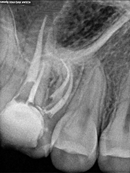

Root Canal Cases